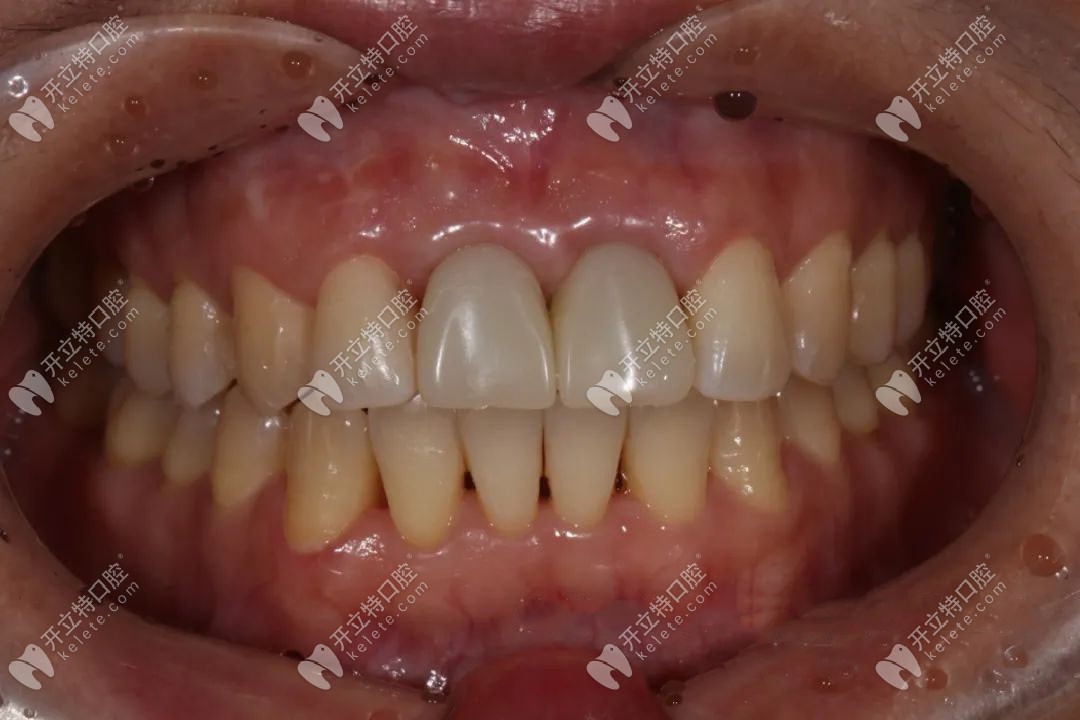

牙齒恢復(fù)后口腔的情況:牙冠和牙齦的密合度良好,沒有出現(xiàn)邊緣漏金屬的現(xiàn)象。